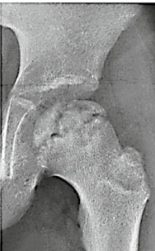

What stage of Perthes disease is this image?

Stage 1

Stage 2

Stage 3

Stage 4

A

Stage 1: avascular necrosis

Stage 4: reossification

Stage 3: remodelling

Stage 2 fragmentation